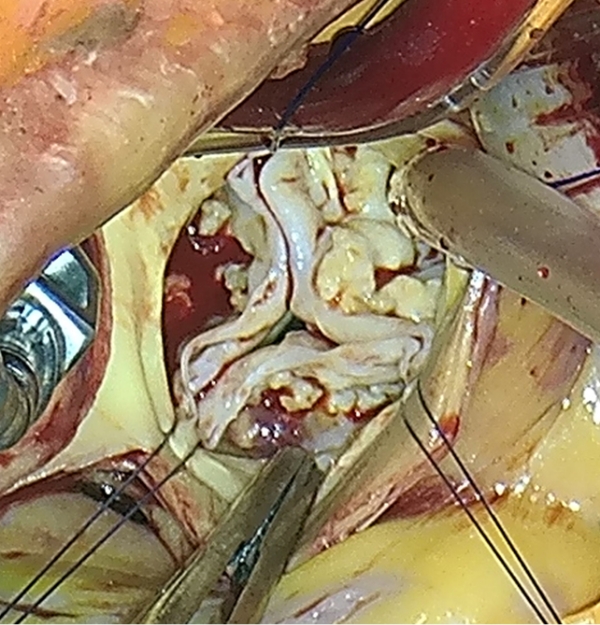

手術の際にバルサルバ洞が拡大して弁尖がお互いに接合しない様子が観察されました。

そのため冠動脈をボタン状に切離し、人工血管の中にバルサルバ洞を切除した後の大動脈基部構造を筒型の人工血管の中に収納しつつ人工血管の断端を左室─大動脈移行部に縫着,さらに大動脈弁尖付着部の遺残大動脈壁を人工血管内側に内縫い固定しました。

人工血管内に収納したのちに弁の接合の様子を内視鏡で観察することで手技の精度を上げています。

この症例では右冠尖に弁形成手技を追加しています。

3つの弁尖が良好に接合しているのが肉眼でもわかります。